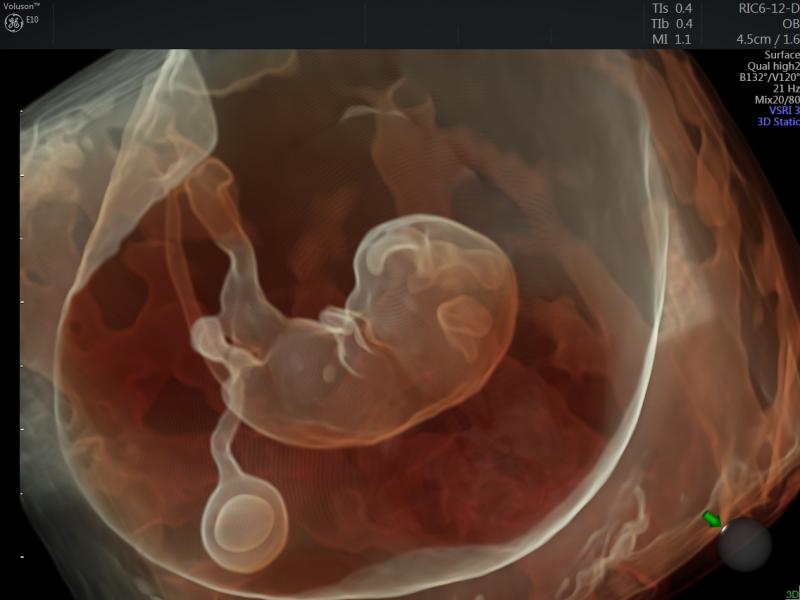

At this year’s scientific assembly and annual meeting of the Radiological Society of North America (RSNA), ContextVision will be demonstrating its wide range of leading 2-D/3-D/4-D imaging enhancement software solutions for ultrasound. The company has made significant upgrades across its product range.